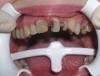

Doc Опубликовано 23 октября, 2008 Поделиться Опубликовано 23 октября, 2008 А почему такая уверенность, что вывалятся? Думаю, что доктору не нравится тот факт, что у всех трех культей есть явное погружение истонченного края под десну и этот факт не был должным образом учтен. Потому возможно микроподтекание, сложная фиксация и невозможность создания адекватного ферула и уступа. Но что касается трех лет, то я бы не был столь категоричен. Срок службы работы зависит от такого большого количества факторов, что по одной фотографии так сразу предсказать его нереально. Ссылка на комментарий

y_veselchak Опубликовано 24 октября, 2008 Поделиться Опубликовано 24 октября, 2008 Думаю, что доктору не нравится тот факт, что у всех трех культей есть явное погружение истонченного края под десну и этот факт не был должным образом учтен. Потому возможно микроподтекание, сложная фиксация и невозможность создания адекватного ферула и уступа. Но что касается трех лет, то я бы не был столь категоричен. Срок службы работы зависит от такого большого количества факторов, что по одной фотографии так сразу предсказать его нереально.Я с большим удовольствием в свое время посетил Вашу лекцию по ВКВ, почерпнул массу интересого и стараюсь. Принимая во внимение исходную картину, вот что получилось во рту - критикуйте Ссылка на комментарий